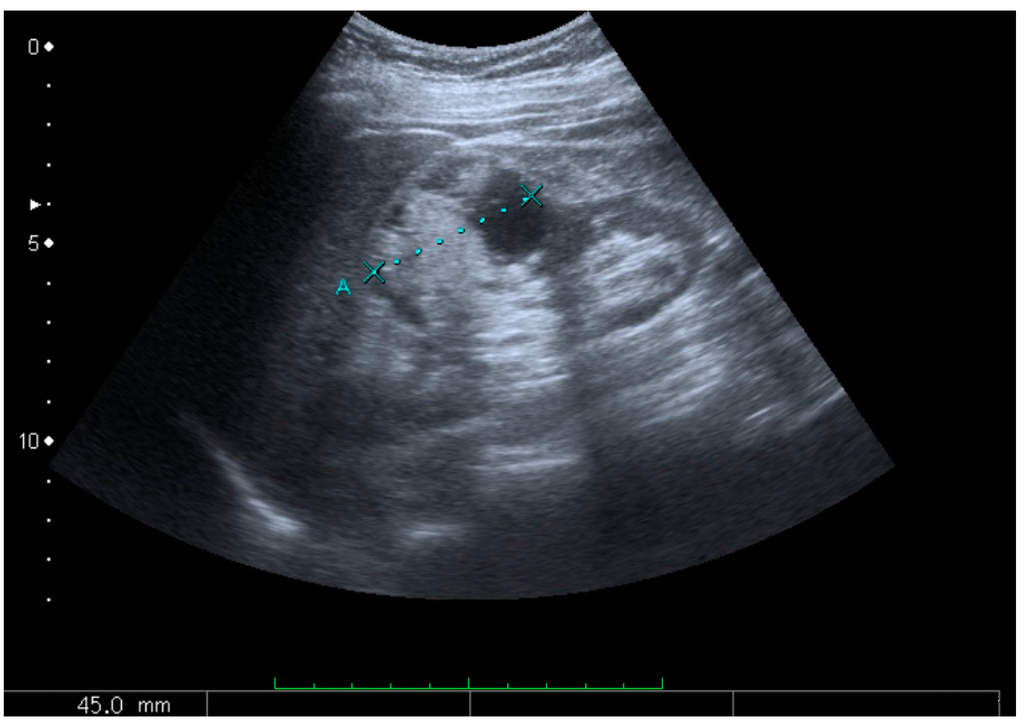

Figure 8. Cortical solid mass, which later was shown to be renal cell carcinoma. Measurement of the solid mass on the US image is illustrated by ‘+’ and a dashed line.

A solid renal mass appears in the US exam with internal echoes, without the well-defined, smooth walls seen in cysts, often with Doppler signal, and is frequently malignant or has a high malignant potential [4]. The most common malignant renal parenchymal tumor is renal cell carcinoma (RCC), which accounts for 86% of the malignancies in the kidney [2]. RCCs are typically isoechoic and peripherally located in the parenchyma, but can be both hypo- and hyper-echoic and are found centrally in medulla or sinus. The lesions can be multifocal and have cystic elements due to necrosis, calcifications and be multifocal (Figure 8 and Figure 9) [2]. RCC is associated with von Hippel–Lindau disease, and with tuberous sclerosis, and US has been recommended as a tool for assessment and follow-up of renal masses in these patients [18].